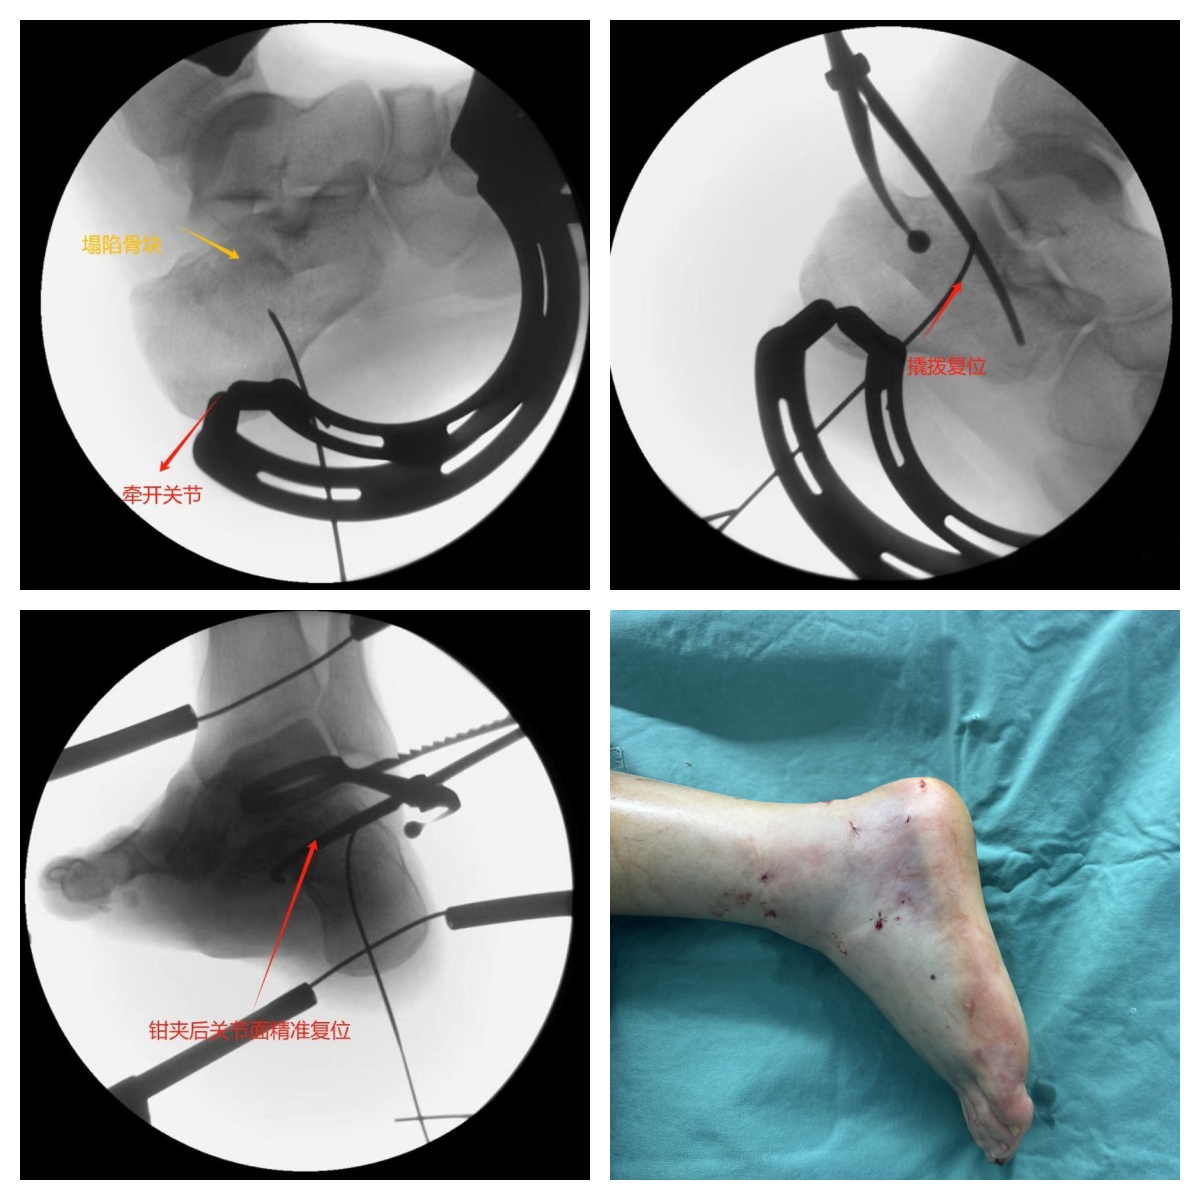

手术最大挑战是精准拼接碎骨,龙承副主任医师团队在X线透视下采用“三步复位法”战略,首先撑开骨折部位的骨头,运用复位针精准调整手术器械,仔细比对每一块碎骨的位置和形态,再将碎骨逐一进行精细复位,最后,使用自主研发的“跟骨复位钳”完成关键的钳夹复位,再用4颗空心螺钉稳稳固定。凭借着精湛的医术和默契的配合,手术团队仅用了30分钟,就成功完成了复位固定,术中出血量几乎为零。

手术效果立竿见影,术后周先生疼痛迅速得到缓解,左脚皮肤上仅留下了几个不易察觉的小孔。当天,在医生的指导下就进行不负重的关节功能锻炼。傍晚时分,周先生带着轻松的笑容顺利出院回家休养。